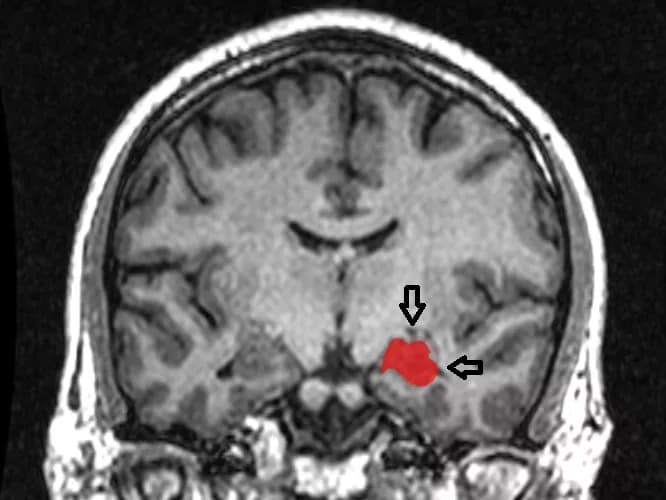

As previous studies have shown, slowing in the participants' gait, or walking speed, was associated with cognitive impairment. However, Rosso's research determined that participants with a slowing gait and cognitive decline also experienced shrinkage of their right hippocampus, an area of the brain important to both memory and spatial orientation. It was the only area of the brain where the researchers found a shrinking volume to be related to both gait slowing and cognitive impairment.